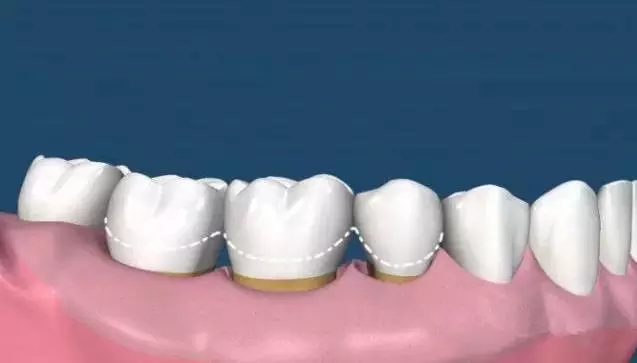

(圖中線條部位為正常牙齦位置,牙齒不光滑的表面布滿牙結(jié)石)

超聲波洗牙清潔掉牙齒表面上的菌斑和牙結(jié)石,牙齒根部的結(jié)石還未去除,且牙齦依然還會(huì)存在紅腫的情況,所以需要繼續(xù)齦下刮治治療。

洗牙后拋光的目的是是牙面更加光滑潔凈,光滑的牙面不容易附著色素和牙結(jié)石。